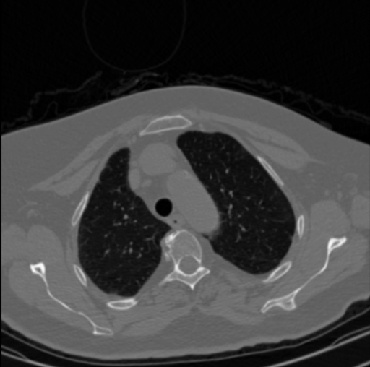

Early and reliable COVID-19 diagnosis based on chest 3-D CT scans can assist medical specialists in vital circumstances. Deep learning methodologies constitute a main approach for chest CT scan analysis and disease prediction. However, large annotated databases are necessary for developing deep learning models that are able to provide COVID-19 diagnosis across various medical environments in different countries. Due to privacy issues, publicly available COVID-19 CT datasets are highly difficult to obtain, which hinders the research and development of AI-enabled diagnosis methods of COVID-19 based on CT scans. In this paper we present the COV19-CT-DB database which is annotated for COVID-19, consisting of about 5,000 3-D CT scans, We have split the database in training, validation and test datasets. The former two datasets can be used for training and validation of machine learning models, while the latter will be used for evaluation of the developed models. We also present a deep learning approach, based on a CNN-RNN network and report its performance on the COVID19-CT-DB database.